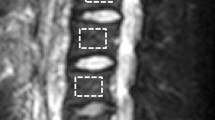

A somewhat different approach for diffusion-weighted imaging is obtained by inserting a single diffusion gradient in a steady-state free-precession (SSFP) sequence. SSFP sequences can be differentiated in three different basic types: those that acquire a free-induction-decay(-FID)-like signal such as the “Fourier-acquired steady-state” (FAST) or “fast imaging with steady precession” (FISP) sequences; those with a spin-echo-like signal such as the contrast-enhanced FAST (CE-FAST) or the reversed FISP (PSIF) sequences; and finally those with fully balanced gradients that acquire a combination of both signals such as the TrueFISP or balanced SSFP (bSSFP) sequences (Oppelt et al. 1986; Bruder et al. 1988; Gyngell 1988). To obtain a reasonable diffusion weighting at short repetition times (TR), particularly the spin-echo-like approaches have proven useful (Le Bihan 1988; Merboldt et al. 1989). Inserting a single (monopolar) diffusion gradient in each TR provides a spin dephasing that is rephased at a later TR (not necessarily at the immediately successive one since the magnetization is switched around between transversal and longitudinal contributions). The delayed rephasing is advantageous in that it provides an increased diffusion weighting—however, it becomes extremely complicated to exactly quantify the diffusion weighting, since it depends not only on the properties of the diffusion gradient, but also on the flip angle, the TR, and the relaxation times of the tissue (Wu and Buxton 1990; Buxton 1993; Deoni et al. 2004). Therefore, diffusion-sensitized SSFP sequences can be used to acquire diffusion-weighted image data (which qualitatively visualize increased ADCs as attenuated signal), but not for the exact quantification of diffusion coefficients. This approach has been demonstrated to be particularly valuable in vertebral bone marrow, since a differentiation of pathological (neoplastic) and benign (osteoporotic) vertebral compression fractures is possible based on the contrast of the diffusion-weighted PSIF sequence (Baur et al. 1998, 2001; Dietrich et al. 2009; Biffar et al. 2011a, b; Dietrich and Baur-Melnyk 2011).

Perfusion properties of bone marrow have been assessed at least qualitatively or semiquantitatively in a relatively large number of studies as summarized, e.g., in (Biffar et al. 2010a). Early examinations of contrast-media uptake dynamics in bone tumors were already performed in the late 1980s demonstrating higher slopes of enhancement in malignant than in benign bone tumors (Erlemann et al. 1989). Further semiquantitative analyses demonstrated, e.g., decreasing bone-marrow perfusion with age (Chen et al. 2001; Montazel et al. 2003) or with osteoporosis (Shih et al. 2004; Griffith et al. 2005). Increasing perfusion indices were demonstrated, e.g., in bone marrow with diffuse tumor infiltration (Rahmouni et al. 2003), in myeloproliferative neoplasms (Courcoutsakis et al. 2011), in idiopathic osteonecrosis of the femoral head (Chan et al. 2011), and in rheumatoid arthritis (Li et al. 2011); increasing contrast enhancement and lower slopes were reported for degenerative endplate changes (Savvopoulou et al. 2011). Reduced perfusion indices at baseline were shown to predict increased reduction of the bone mineral density in the femoral neck after 4 years (Griffith et al. 2011). Significantly different semiquantitative perfusion parameters were found in neoplastic and normal bone (D’Agostino et al. 2010) as well as in osteoporotic and neoplastic vertebral compression fractures (Tokuda et al. 2005); for the latter differentiation, time-intensity-curve patterns were also reported to be valuable (Chen et al. 2002). Another recent study showed a generally good reproducibility of the measurement of these perfusion-related indices in the bone (Griffith et al. 2009).

Only few results have been published with fully quantitative perfusion evaluation of the bone marrow. Permeability-related quantitative parameters of bone marrow evaluated in patients with multiple myeloma yielded increased values for the contrast-agent exchange rate constant of tissue with (high-degree) infiltration (Moehler et al. 2001; Nosas-Garcia et al. 2005). Permeability constants, elimination rates, and the perfusion amplitude were found to be reduced in osteoporotic subjects using a modified Brix model (Ma et al. 2010) and increased in bone marrow edema relative to normal bone (Lee et al. 2009). Typical blood flow and volume parameters in normal-appearing vertebral bone marrow are reported to be about 15 mL/(100 mL min) and about 5 mL/100 mL, respectively, with a very low permeability-surface-area product (Biffar et al. 2010b, 2011b). These values are significantly increased in osteoporotic vertebral fractures as summarized in Table 2. An improved analysis of bone-marrow perfusion data has been proposed to include effects of the fat fraction within the tissue which is about 30–50 % in healthy bone marrow (Biffar et al. 2010c). Assuming that the contrast-agent influences only the T 1 relaxation of the water protons and considering the different baseline relaxation rates of the fat and water fraction in bone marrow, this more sophisticated perfusion analysis yielded a significantly increased value of plasma volume in healthy bone marrow and a significantly decreased value of plasma flow in vertebral fractures (Table 2).